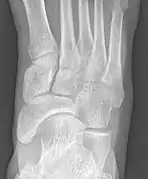

![]() X-ray of the foot showing an accessory navicular bone | |

An accessory navicular bone is an accessory bone of the foot that occasionally develops abnormally in front of the ankle towards the inside of the foot. This bone may be present in approximately 2-21% of the general population and is usually asymptomatic.[1][2][3] When it is symptomatic, surgery may be necessary.